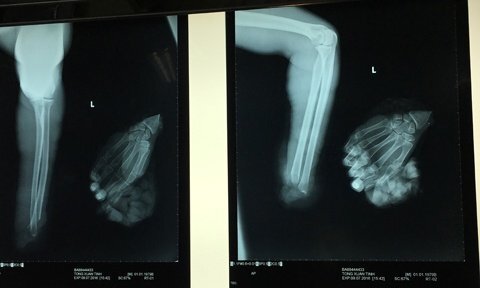

Do làm việc bất cẩn, T. bị máy xén giấy cắt lìa bàn tay trái, sau đó được đồng nghiệp sơ cứu, cho tay vào thùng đá đi cấp cứu.